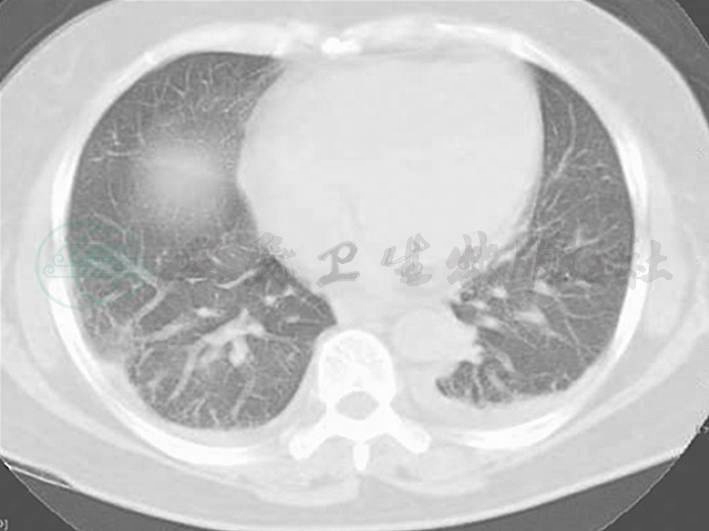

图1 胸腹部CT

两肺纹理增多增粗,两下肺背侧见斑片高密度影,边界模糊;两侧少量胸腔积液(7月8日)